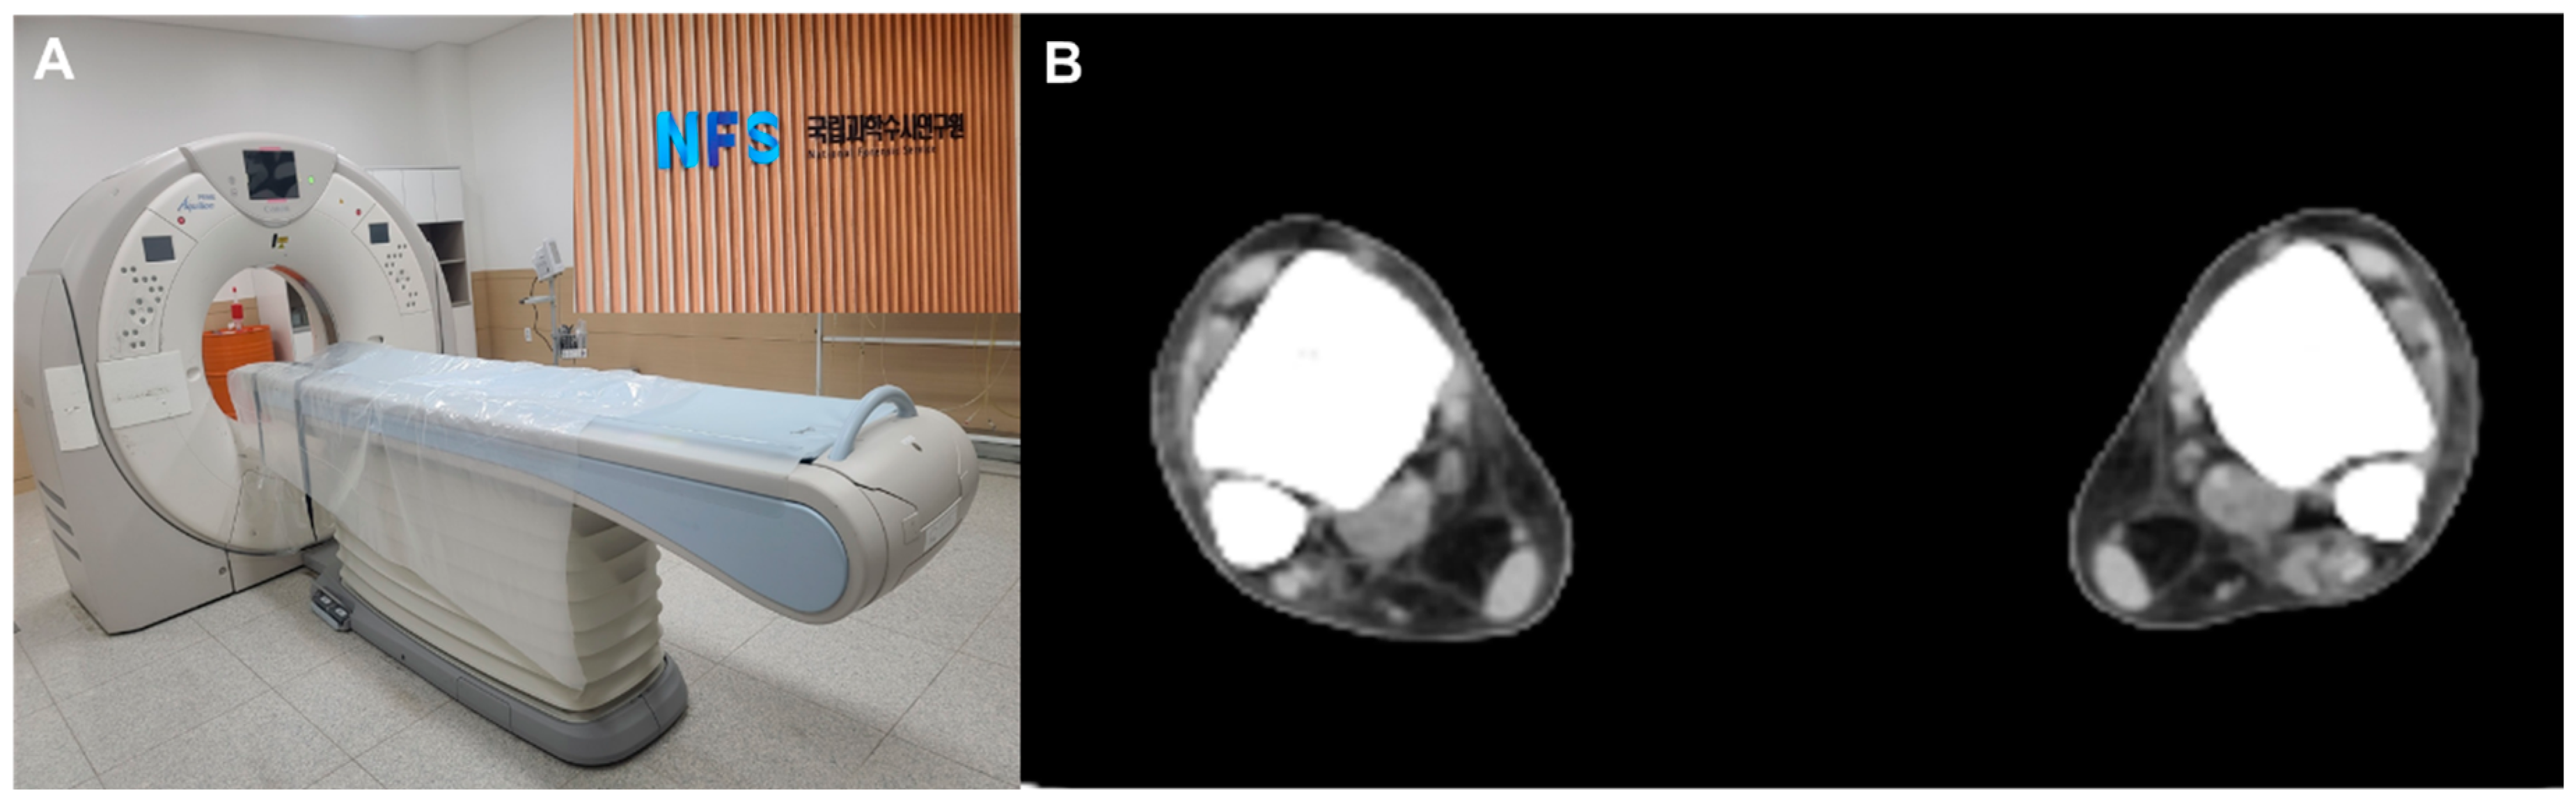

On arrival at NFC, all subjects were screened with bilateral ankle CTs (Aquilion PRIME TSX-303A, CANON Medical Systems Corporation, Tokyo, Japan) (Figure 1A). To provide consistent axial slices parallel to the plafond, the vertical axis of the tibia and the horizontal axis of the plafond were used as reference axes. In addition, the bimalleolar axis, a line perpendicular to the line connecting anterior aspects of the medial and lateral malleoli, was used as a reference to guarantee neutral rotation [,]. For each CT scan, a single axial image 1 cm above the tibial plafond, a level where the length of the distal anterior tibial tubercle is the greatest, was selected for measurement [] (Figure 1B).

Figure 1.

(A) All subjects were screened postmortem computed tomography, (B) A single axial image 1 cm above the tibial plafond, a level where the length of the distal anterior tibial tubercle is the greatest, was selected for measurement.